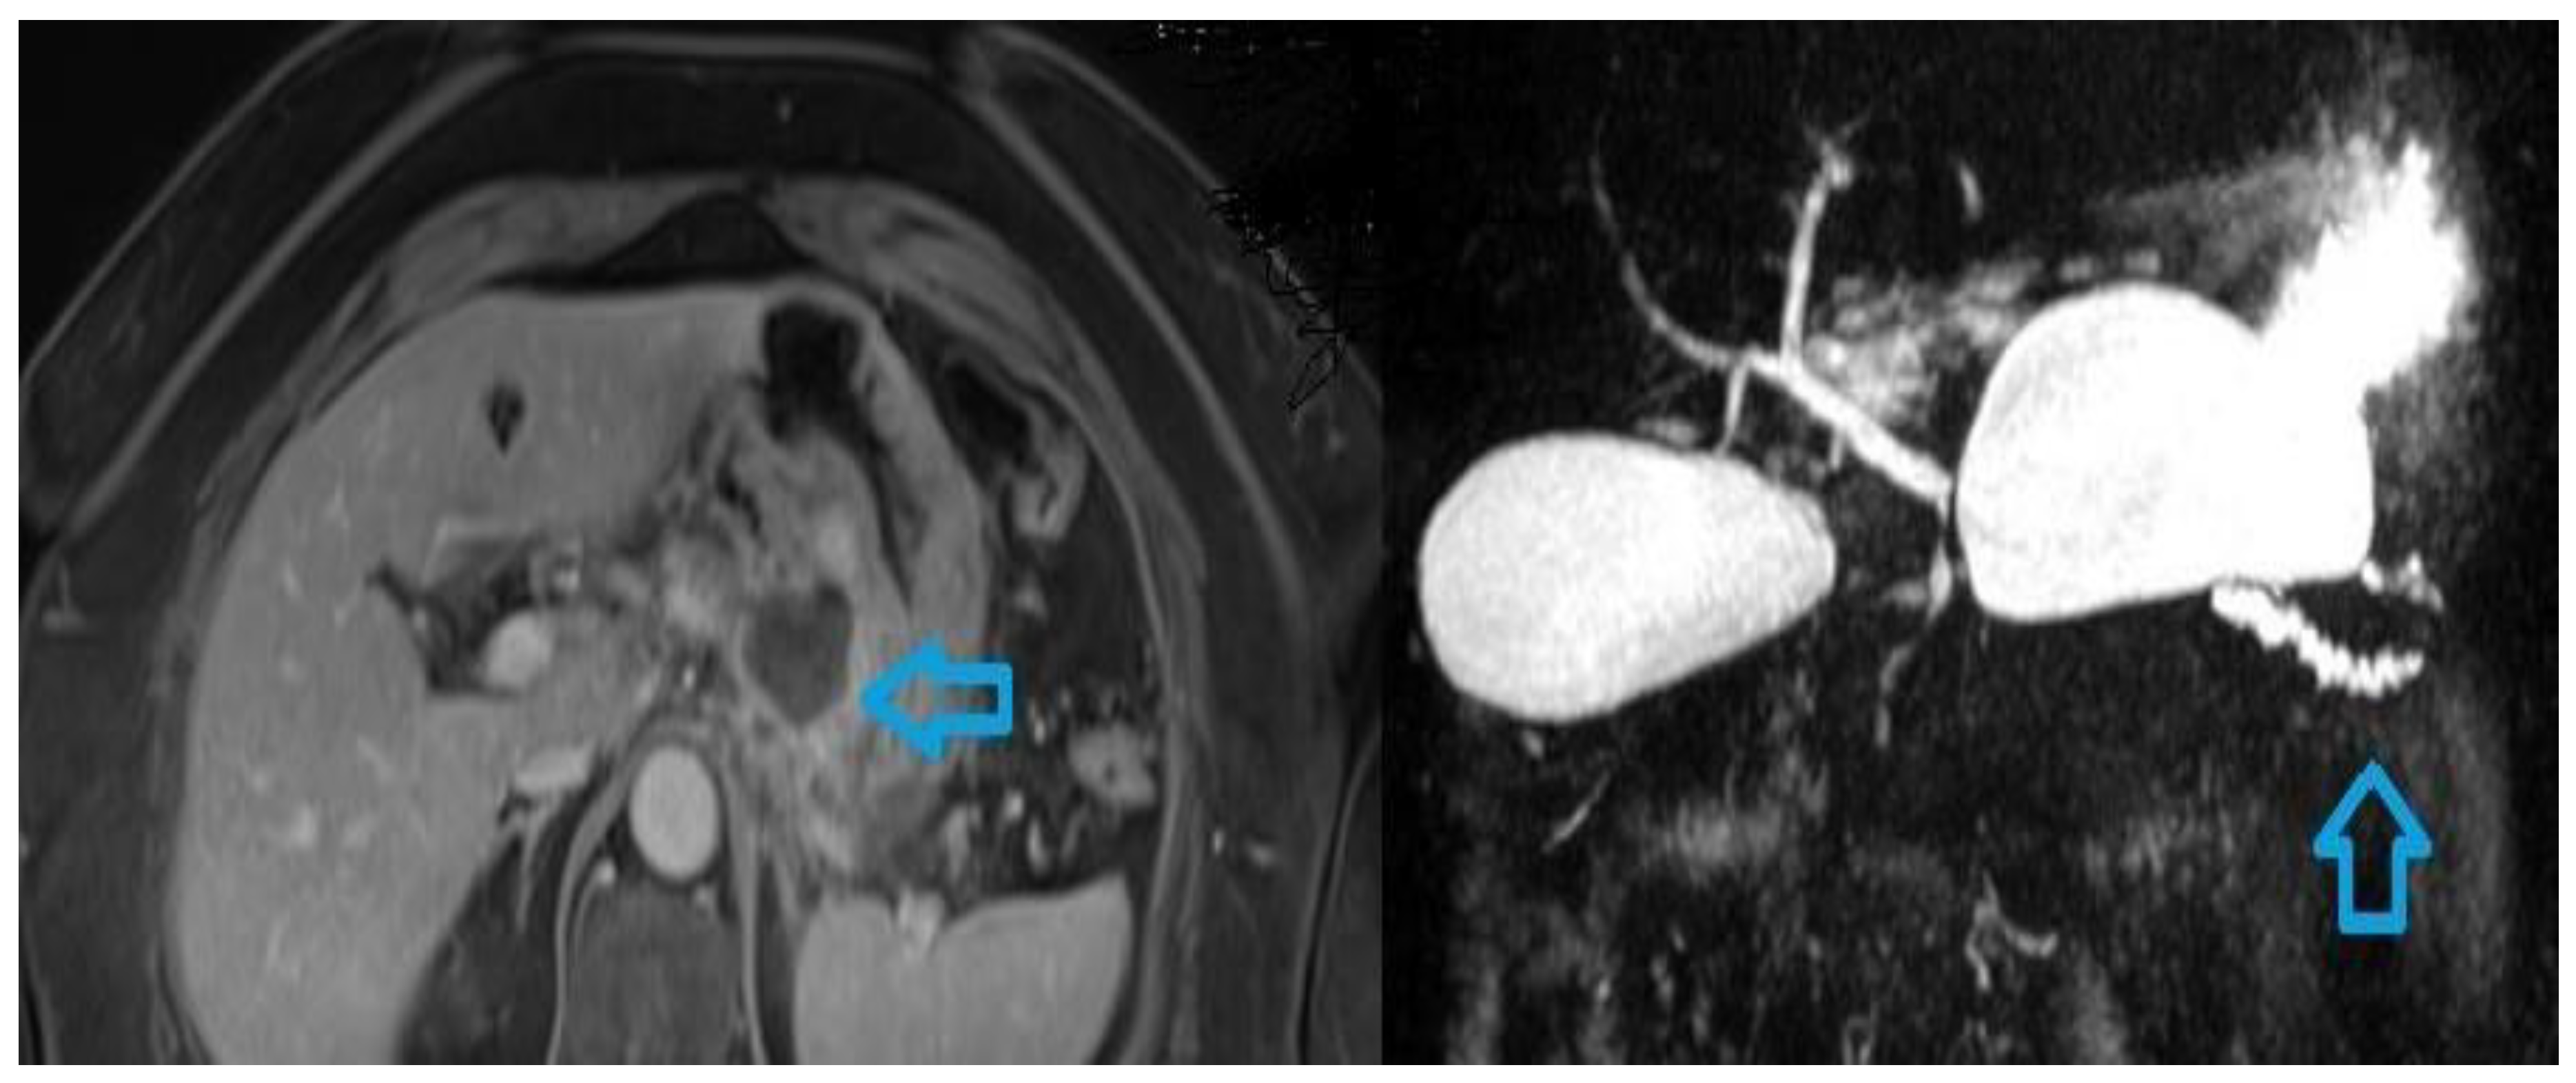

Figure 2. MRI appearance of acute pancreatitis and complications. The image on the left shows a case of necrotising pancreatitis with a fluid collection with irregular and thick wall and rim enhancement compatible with WON (arrow). The MRCP image on the left shows, in a patient with previous necrotising pancreatitis, a fistula (arrow) between pancreas and peripancreatic fat producing a fluid collection.